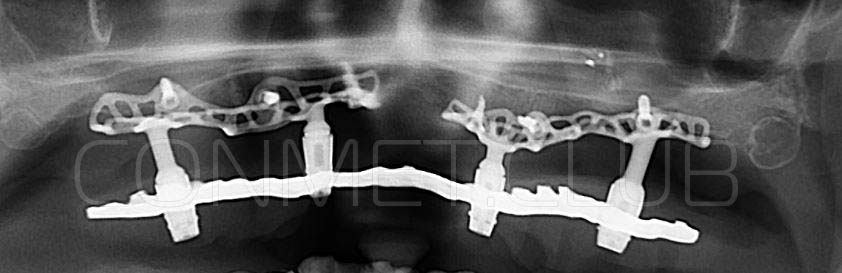

Посмотрите на небольшом клиническом примере новый подход к конструированию имплантата по сравнению с имплантатами описанными в начале этой статьи.

Первый вывод к которому мы пришли, это то, что для данных конструкций имплантатов сохранять внутренний интерфейс с шестигранником и конусом Морзе нецелесообразно из-за ограничения возможностей современной 3D печати титана. Кроме того, техническая обработка после 3D печати такого интерфейса представляет значительные трудности и ведет к неоправданному увеличению цены. Поэтому пришли к единодушному мнению, что лучший вариант-это опорные элементы полностью повторяющие абатменты-мультиюниты.

Посмотрите на приведенные выше работы и вы обратите внимание, что перфорации в теле имплантатов подчиняются скорее "художественным" принципам нежели биомеханическим. Поэтому уже в 2018 году не только изготовление, но и конструирование имплантатов было целиком передано сотрудникам Конмет. Это в значительной степени повысило качество самих имплантатов, но по вполне понятным причинам (таких грамотных инженеров-конструкторов по определению не может быть много) резко удлинились сроки изготовления. При определенных случаях, когда после удаления зубов кость еще не окончательно закончила ремоделировку, срок с момента КТ по которому моделируют субпериостальный имплантат, до операции может носить критический характер. Т.е., чем дольше время изготовления, тем больше вероятность того, что имплантат не полностью будет соответствовать рельефу подлежащей костной ткани.